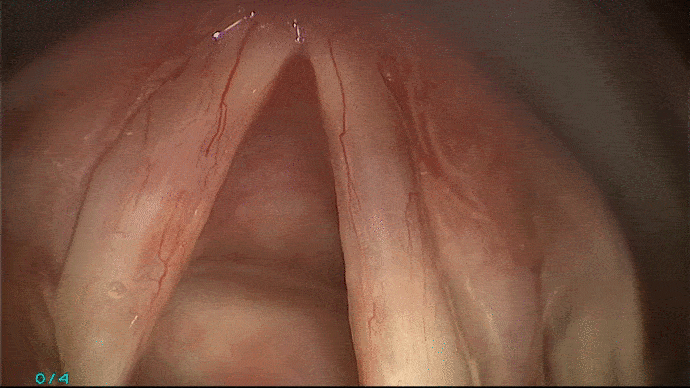

Votre voix peut rester altérée, voire aggravée du fait de la présence de lésions cicatricielles, ou encore d’une récidive de votre pathologie initiale.

La phono-chirurgie et la micro-chirurgie laryngée est une intervention sous anesthésie générale réalisée en laryngoscopie directe en suspension et permet :

L’instrumentation comporte une suspension qui libère les mains de l’opérateur. Le laryngoscope est introduit par la bouche et s’appuie sur les dents par l’intermédiaire d’une protection dentaire. Les instruments sont utilisés sous contrôle du microscope opératoire ou des optiques. Un repos vocal post opératoire vous sera dans certains cas préconisé.